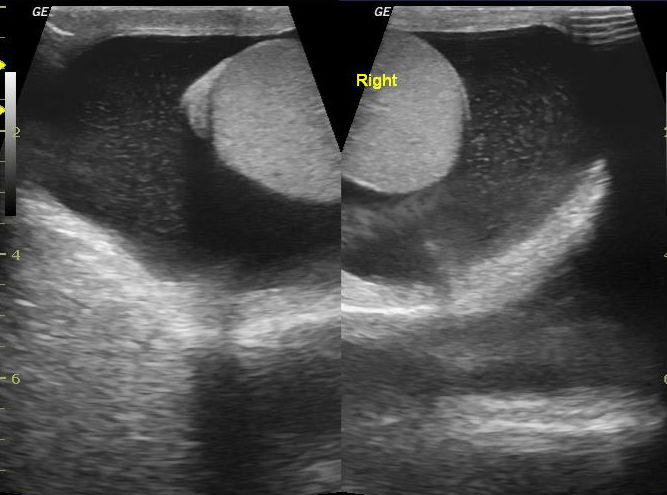

Особенности УЗИ при определении пола ребенка

Раздел: Идеи и советы